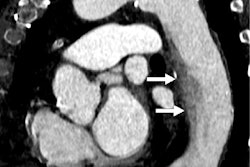

Coronary CT angiography has relatively low specificity for evaluating coronary artery disease, especially when it comes to assessing whether lumina are open in the presence of heavy calcifications due to calcium blooming, Koons said.

"[The quality of] coronary CTA is primarily limited by the spatial resolution of the system," she explained.

The two readers identified stenotic lesions in 22 test patients. Koons' team reported that ILUMENATE reduced percent diameter stenosis by an average of 5.3% (p < 0.001) and that the two readers preferred ILUMENATE images in all 22 cases.

The bottom line? ILUMENATE shows promise for improving the evaluation of lesions in individuals with heart disease, according to the researchers.

"The … improved lumen visibility with ILUMENATE could allow ultrahigh resolution cardiac CT to be performed using conventional … CT scanners and allow for more accurate assessment of stenotic lesions in patients with coronary artery disease," Koons and colleagues noted.